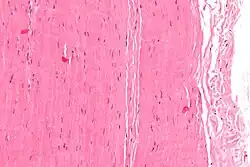

The characteristic substances inside the extracellular matrix of soft tissue are the collagen, elastin and ground substance. Normally the soft tissue is very hydrated because of the ground substance. The fibroblasts are the most common cell responsible for the production of soft tissues' fibers and ground substance. Variations of fibroblasts, like chondroblasts, may also produce these substances.[4]

The collagen fibers are approximately 1-2 μm thick. Thus, the resolution of the imaging technique needs to be approximately 0.5 μm. Some techniques allow the direct acquisition of volume data while other need the slicing of the specimen. In both cases, the volume that is extracted must be able to follow the fiber bundles across the volume. High contrast makes segmentation easier, especially when color information is available. In addition, the need for fixation must also be addressed. It has been shown that soft tissue fixation in formalin causes shrinkage, altering the structure of the original tissue. Some typical values of contraction for different fixation are: formalin (5% - 10%), alcohol (10%), bouin (<5%).[15]